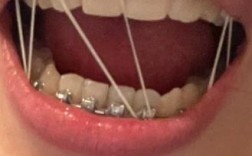

预防牙种深了的关键在于术前精准评估和术中精细操作:术前需拍摄CBCT三维重建,测量牙槽骨高度、宽度、神经管位置,制作手术导板辅助定位;术中逐级备洞,每深入1mm即测量深度,控制植入速度和方向,避免盲目追求初期稳定性而过度植入。